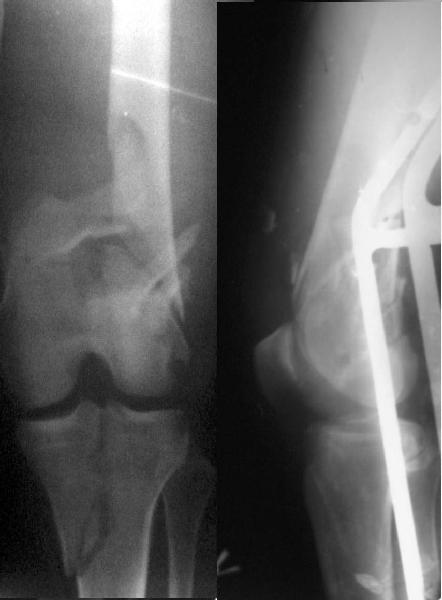

This is what we have done... As generally true for LISS look at the bone not the hardware.

There are two more srews above. The one not completely in got damaged head.

Zsolt

And why LISS is superior here than nail?

Look what we would have done.

I would not say that the LISS is superior to the nail. If I would, I had not post original mail. I wanted to generate discussion. Your option is a very viable one. I feel a little bit shaky the distal femur, but it is just gut feeling no science behind it. Any way nice fixation, congarts!